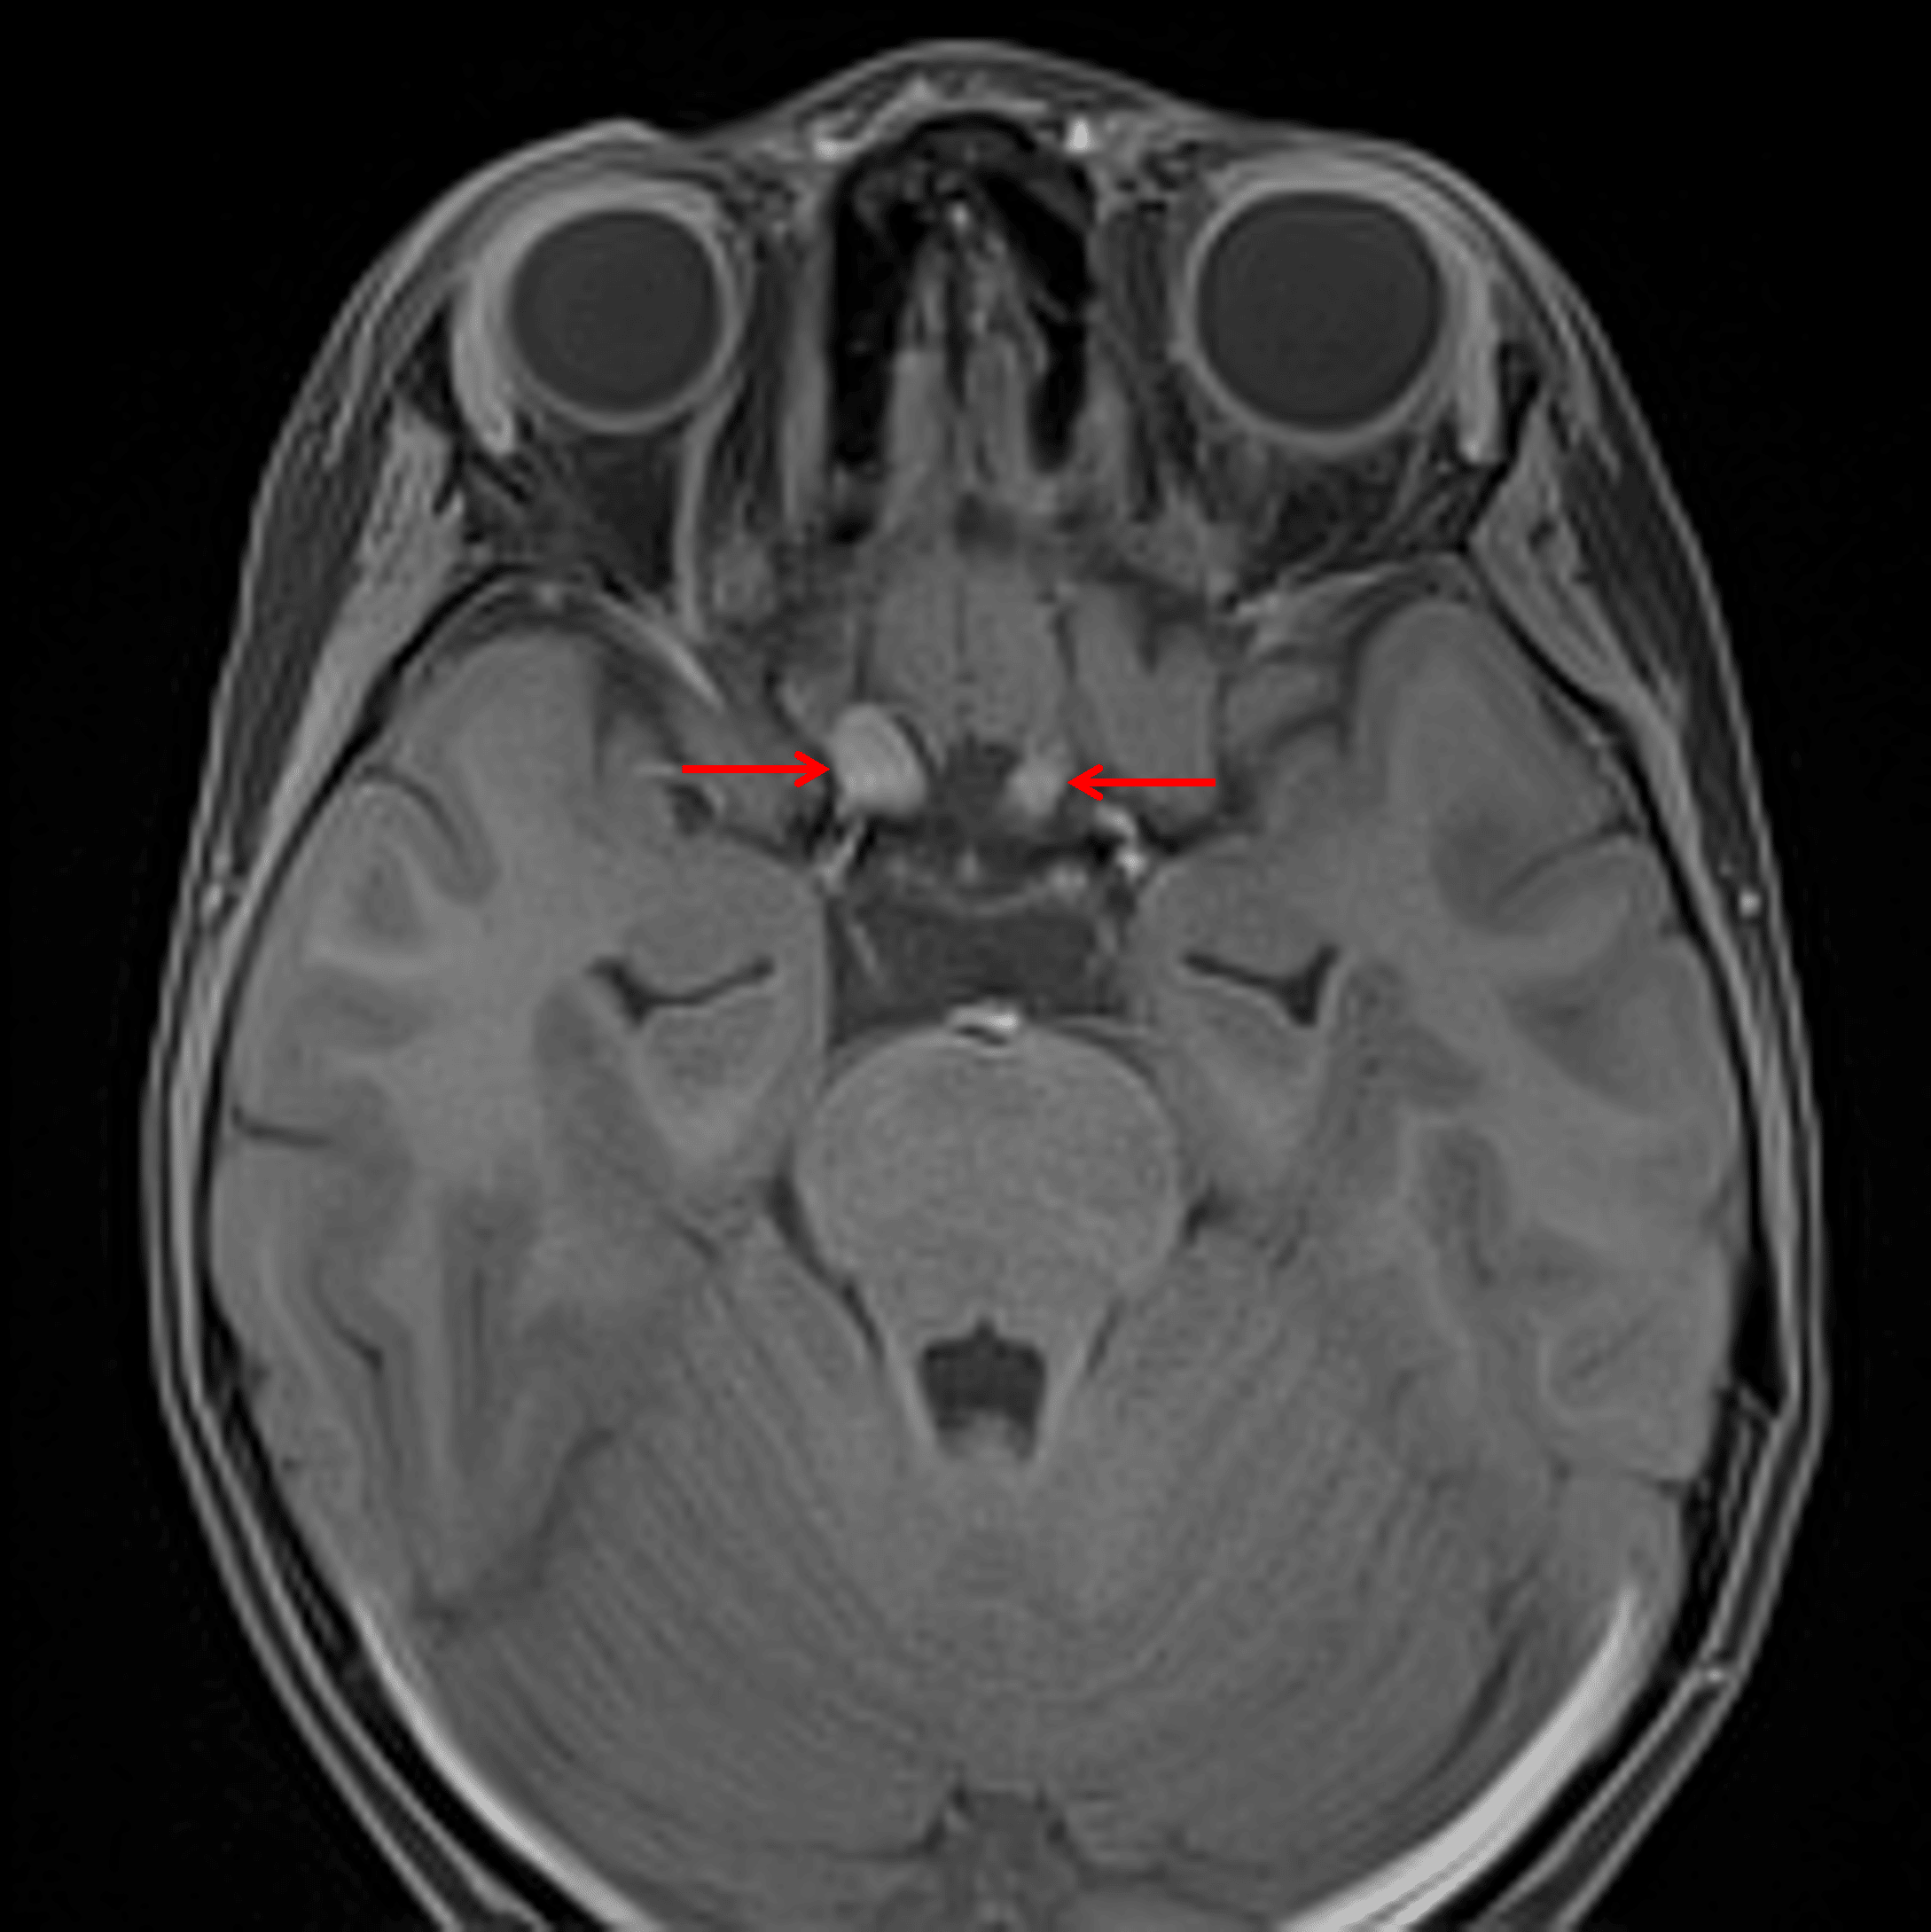

Enlargement of the right greater than left prechiasmatic optic nerves (red arrows), consistent with optic pathway glioma in this patient with NF-1.

- Enlargement of the right greater than left prechiasmatic optic nerves and optic chiasm, likely representing optic pathway glioma